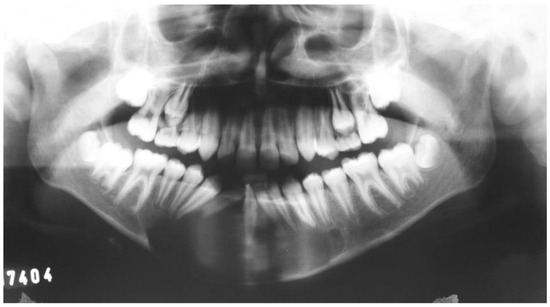

2.2. Case 2